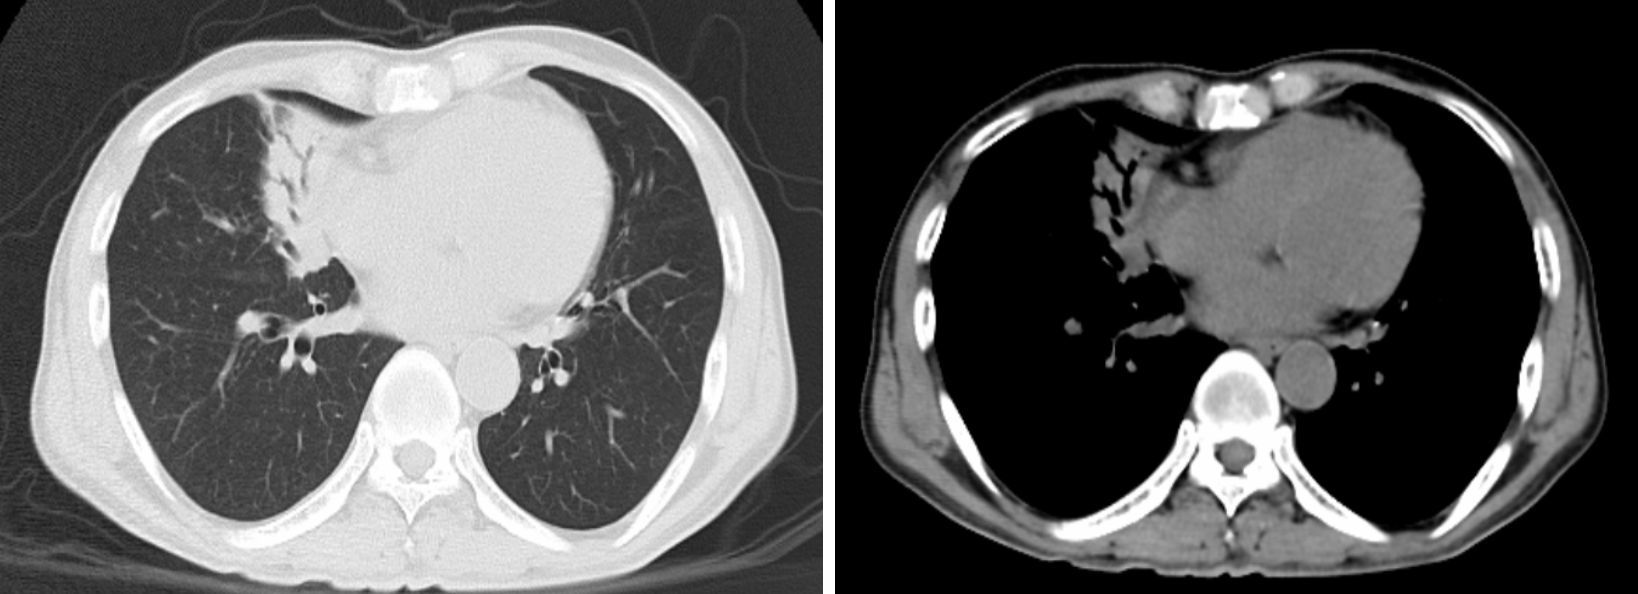

輔助檢查:外周血2013年12月11日白細胞計數為20.63×109/L,中性粒細胞0.860。2013年12月26日白細胞計數為12.32×109/L,中性粒細胞0.797;尿素氮8.05 mmol/L,肌酐209 μmol/L,堿性磷酸酶(ALP)144 U/L,谷氨酰轉肽酶(GGT)342 U/L; 多次痰涂片抗酸染色均陰性,痰培養陰性,PPD試驗陰性,結核抗體陰性,支原體、衣原體及軍團菌抗體均陰性,血清腫瘤標志物、抗核抗體(ANA)、抗可溶性抗原(ENA)、抗dsDNA正常,血培養見放線菌(圖 1),送至復旦大學醫學院病原微生物教研室鑒定。CT引導下經皮肺穿刺活檢病理找到菌絲及孢子,擬診斷為真菌感染。胸部CT(2013年12月18日)示右肺中葉大片高密度影,伴空氣支氣管征(圖 2)。

肺放線菌病的影像學表現無特異性[14],可表現為實質性團塊影、片狀影、結節、支氣管充氣征、空洞、胸腔積液、縱隔淋巴結腫大及胸膜增厚,有學者認為肺放線菌病CT增強掃描外周延遲強化和實性部分逐漸強化為其特點[15-16]。病變部位以左下葉居多,可能與吸入途徑感染有關;右中葉次之。本例患者影像學主要表現為右中葉肺炎,支氣管鏡檢查示右肺中葉和下葉黏膜充血水腫,管腔狹窄。目前,罕見報道肺放線菌病PET表現,Lee等[17]在2012年歐洲胸部影像學年會報告顯示病灶18F-FDG攝取值增高,SUV平均為5.73±2.74,與肺癌難以鑒別。